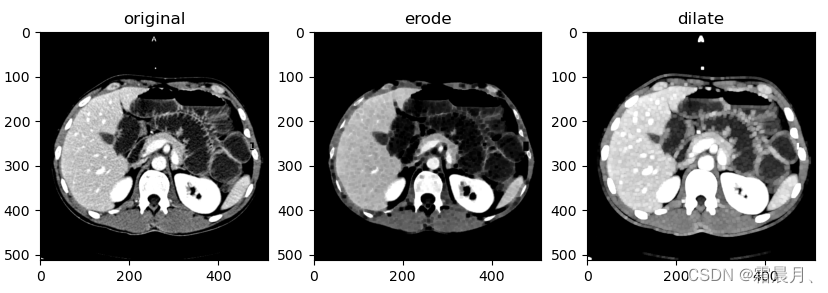

1. 腐蚀(Erode)

将物体的边缘加以腐蚀。拿一个宽m高n的矩形作为kernel,对图像中的每一个像素进行扫描,扫描后的图像的每个像素点和原图的位置对应,同时和扫描时kernel的中心点对应。

用kernel遍历原图的所有像素,每遍历一次就将对应位置的像素点更改为kernel中的最小值。

与操作也就是最小值替换中心像素。

- 对象大小减少1个像素(3*3)

- 平滑对象边缘

- 弱化或者分割图像之间的半岛型连接

2. 膨胀(Dilata)

腐蚀的反操作:膨胀能对图像的边界进行扩展,就是将图像的轮廓加以膨胀。

用kernel遍历原图的所有像素,每遍历一次就将对应位置的像素点更改为kernel中的最大值。

或操作也就是最大值替换中心像素

- 对象大小增加一个像素(3*3)

- 平滑对象边缘

- 减少或者填充对象之间的距离

2. 膨胀与腐蚀

im = imread('zebras.jpg', as_gray=True)

im = rgb2gray(im)

selem = square(5) #square(2) # #square(4) #disk(6)

# 腐蚀

eroded = erosion(im, selem)

# 膨胀

dilated = dilation(im, selem)